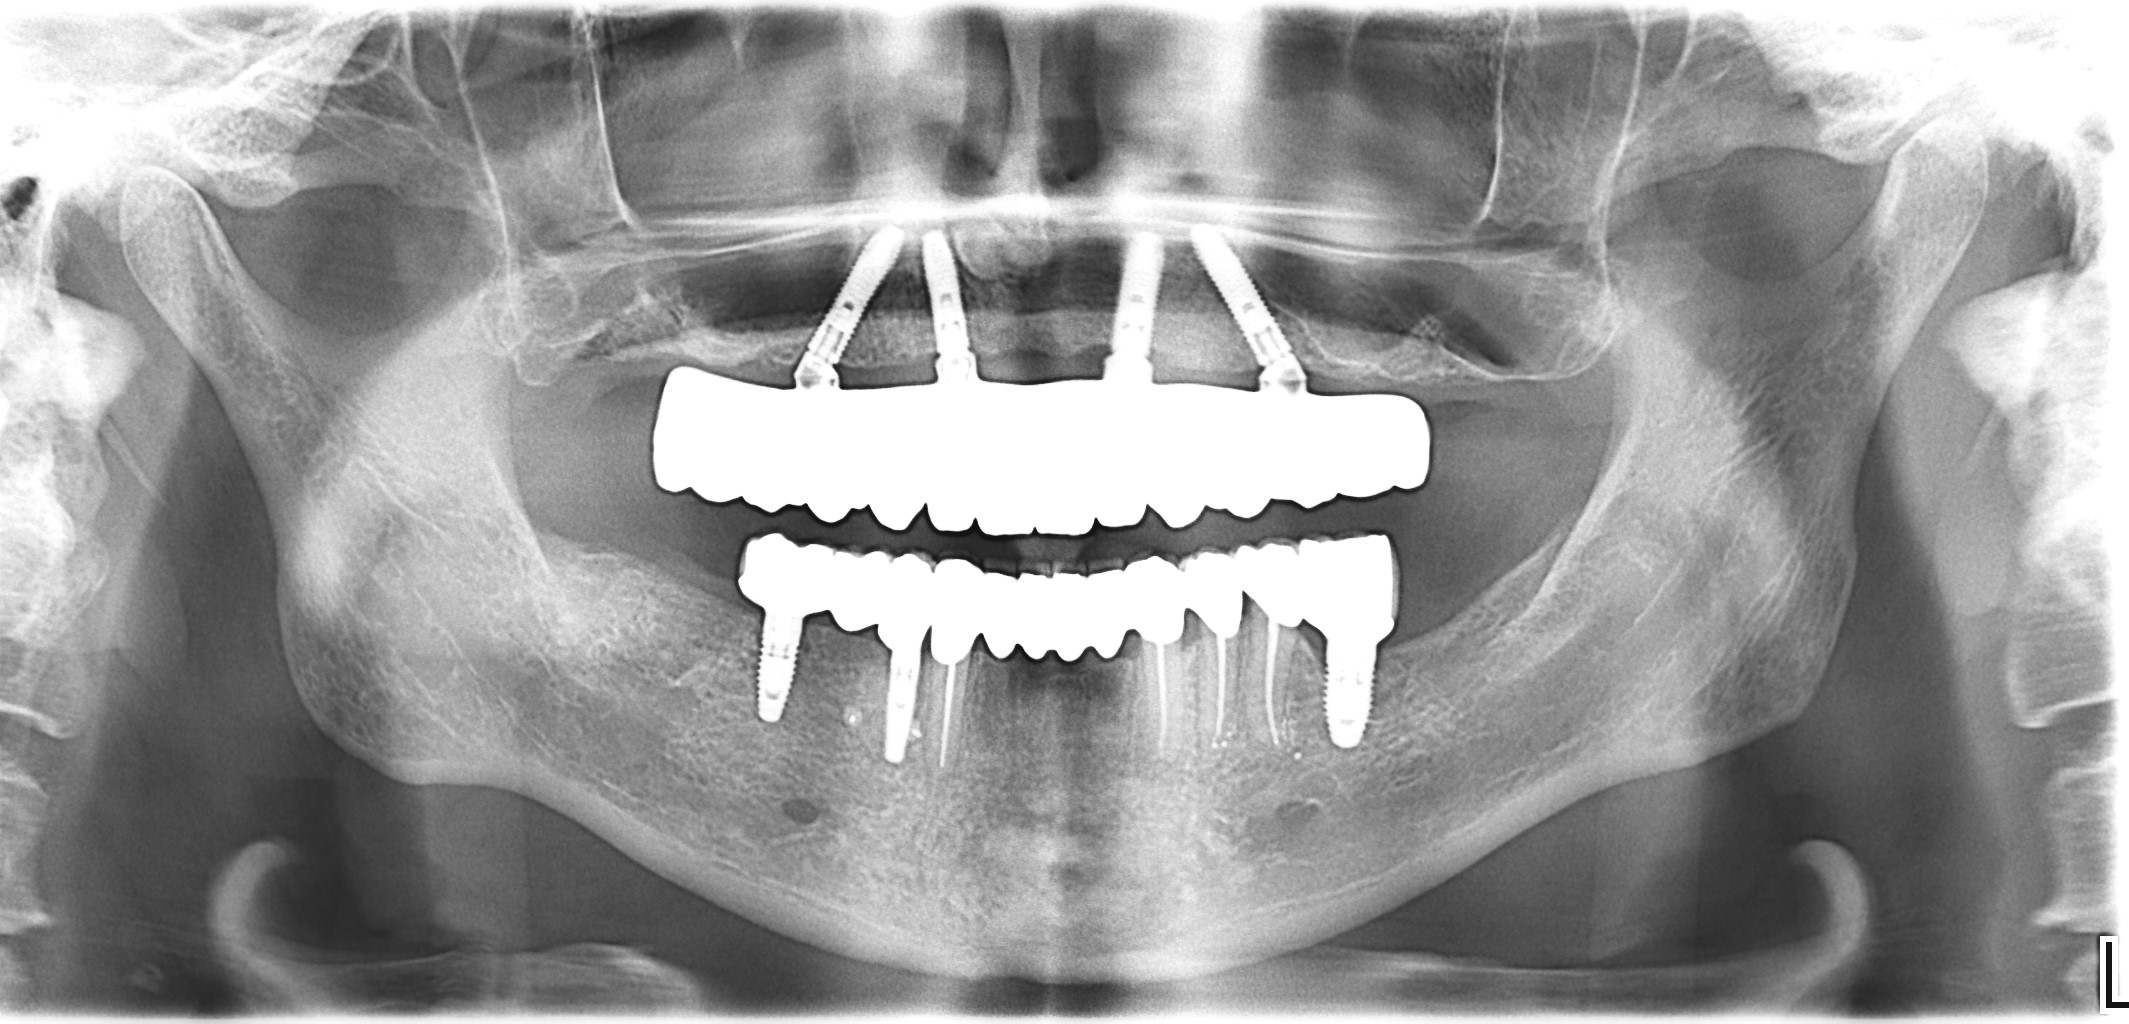

На панорамной рентгенограмме после окончания протезирование с постоянными конструкциями обоих челюстей мы видим стабильный уровень костной ткани вокруг каждых имплантатов и зубов (рис. 50).